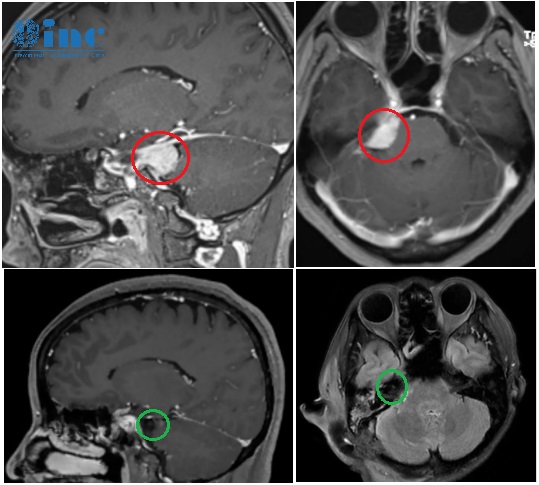

腦膜瘤影像

病灶現(xiàn)在已經(jīng)不存在了。影像上沒(méi)有任何腫瘤殘留,也沒(méi)有復(fù)發(fā),一切都如預(yù)期般良好,她現(xiàn)在不需要任何輔助治療。 開(kāi)顱術(shù)后3個(gè)月,我收到了INC巴特朗菲教授的術(shù)后隨訪報(bào)告。最讓我激動(dòng)的是,教授還在報(bào)告上用中文寫了四個(gè)字:不能更好。這一刻我知道,這場(chǎng)與腦膜瘤的抗?fàn)?,我贏了。 38歲的我經(jīng)營(yíng)...

開(kāi)顱術(shù)后3個(gè)月,我收到了INC巴特朗菲教授的術(shù)后隨訪報(bào)告。最讓我激動(dòng)的是,教授還在報(bào)告上用中文寫了四個(gè)字:“不能更好”。這一刻我知道,這場(chǎng)與腦膜瘤的抗?fàn)帲亿A了。